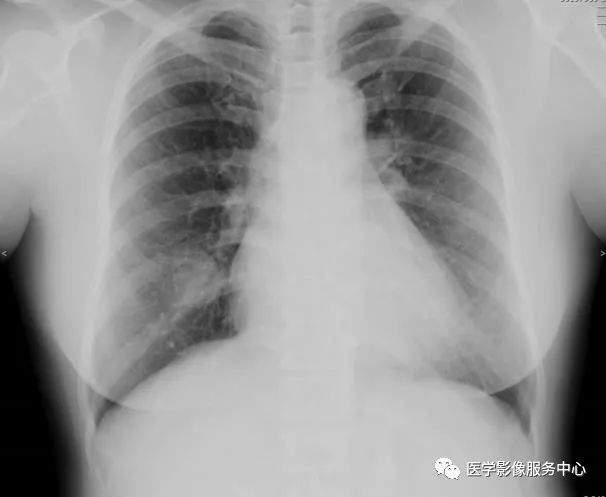

胸片正侧位:右肺中叶见一圆形边界清楚的高密度结节影。 病变中似有“空气新月征”。